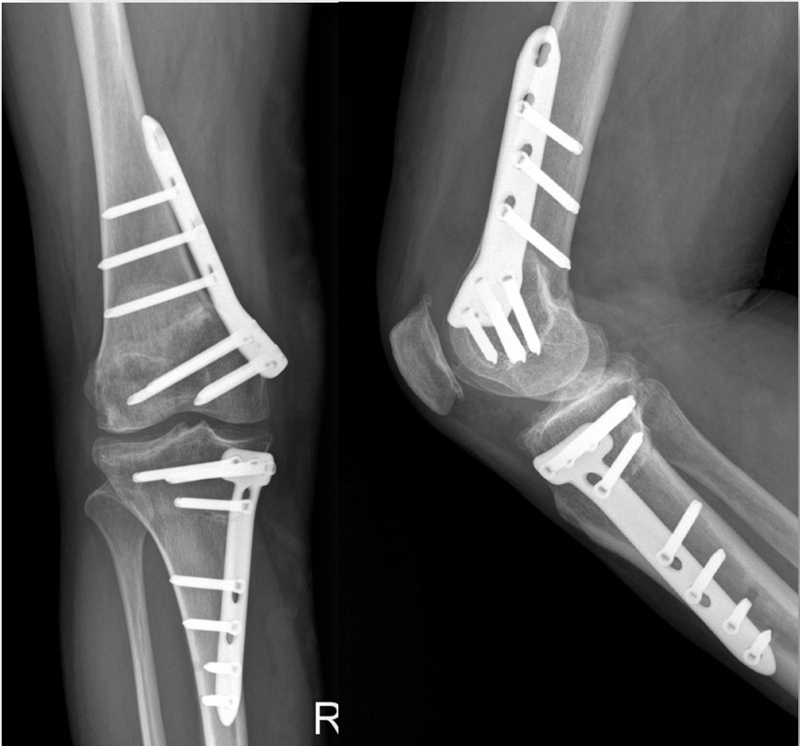

患者二,女性,膝外翻,膝外侧疼痛。通过做畸形分析后发现,该患者同时存在股骨侧畸形、胫骨侧畸形和关节内畸形(LDFA=82°,MPTA=104°,JLCA=6°)。

对于这类病人如何进行术前设计的关键点就在于目标力线应如何设计。要在骨性截骨的时候纠正骨性畸形,关节内畸形要通过关节内的方法解决。因为JLCA不平行,所以要同时画股骨侧关节线和胫骨侧关节线,并垂直于股骨侧关节线做出股骨侧目标力线,垂直于胫骨侧关节线做出胫骨侧目标力线。

根据各自目标力线,分别计算股骨内侧闭合和胫骨内侧闭合角度。

此患者股骨内侧闭合6°,经股内侧闭合13°。

术后影像